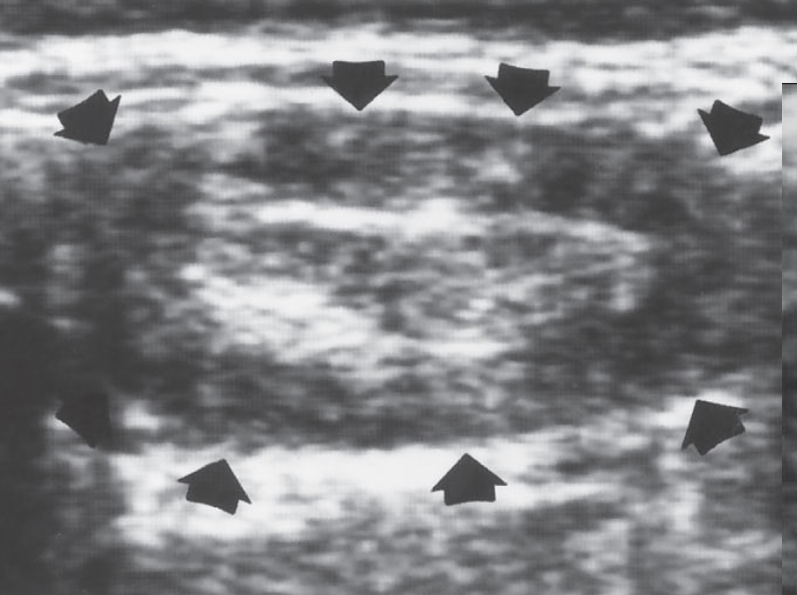

what is shown?

target sign in longitudinal plane indicating hypertrophic pyloric stenosis (HPS)